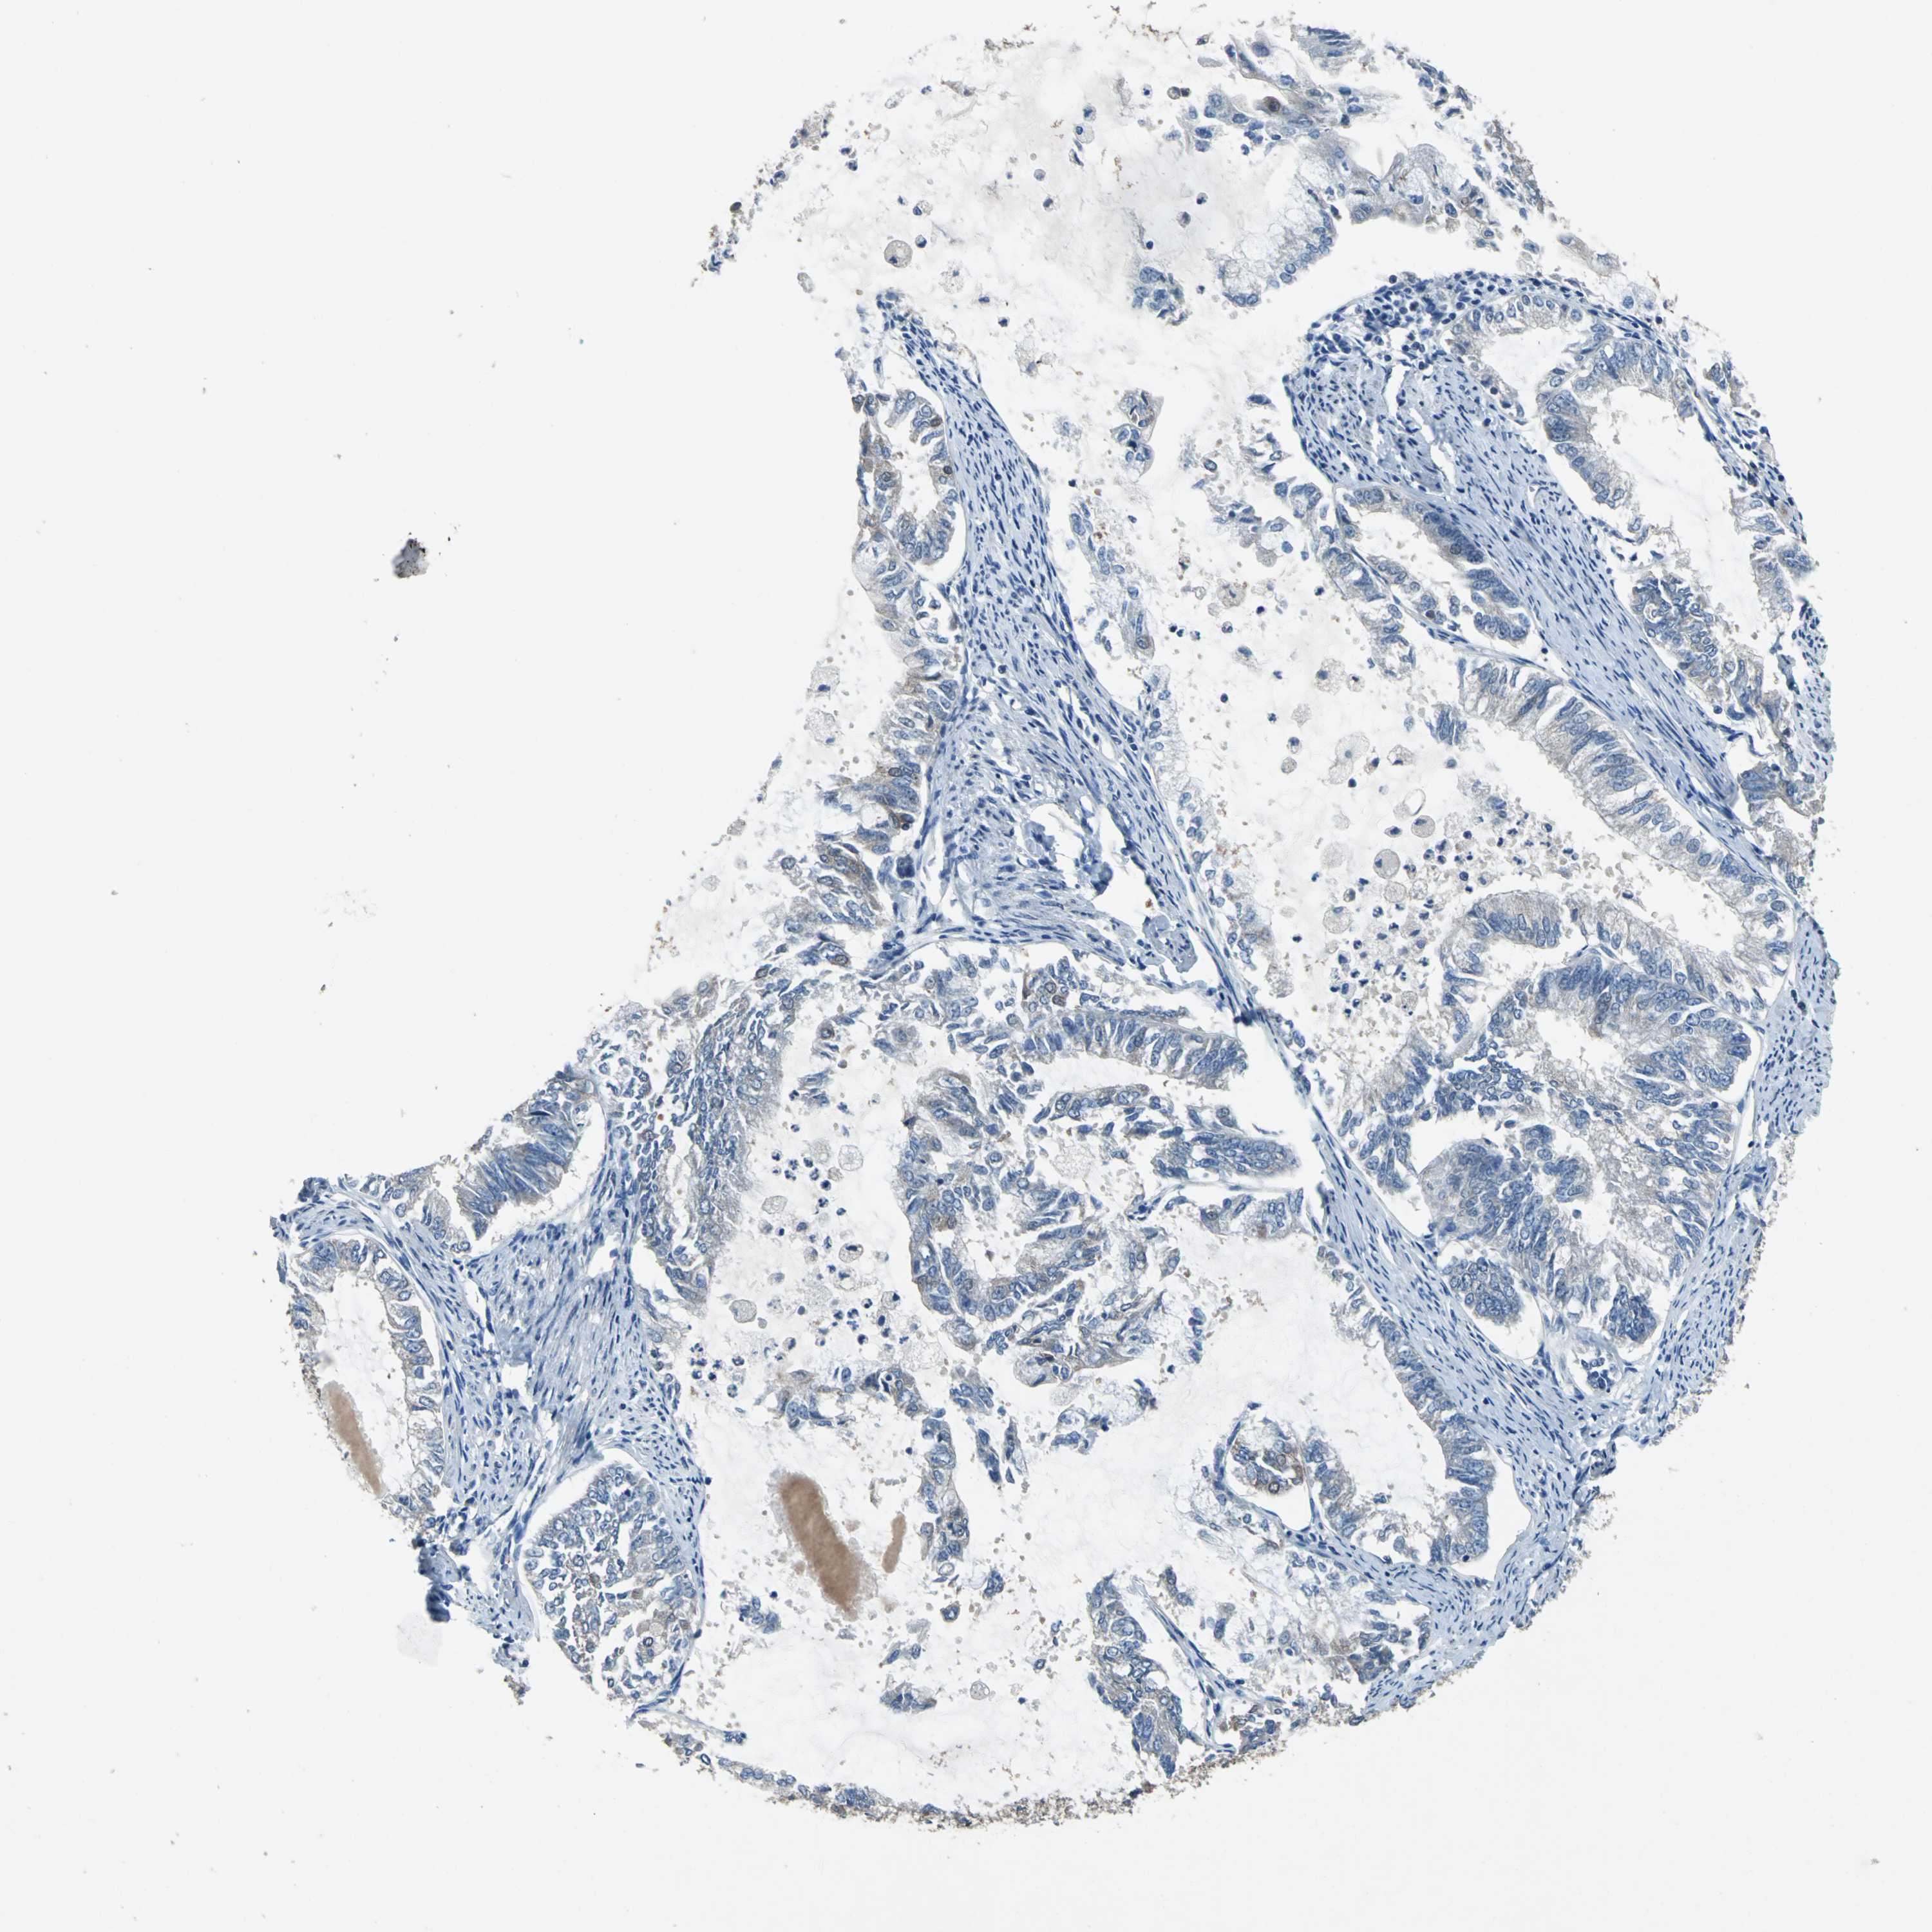

ENDOMETRIAL CANCER - Protein expressioni

A mouse-over function shows sample information and annotation data. Click on an image to view it in a full screen mode. Samples can be filtered based on level of antibody staining by selecting one or several of the following categories: high, medium, low and not detected. The assay and annotation is described here.

Note that samples used for immunohistochemistry by the Human Protein Atlas do not correspond to samples in the TCGA dataset.

Antibody stainingi

Antibody staining in the annotated cell types in the current human tissue is reported as not detected, low, medium, or high, based on conventional immunohistochemistry profiling in selected tissues. This score is based on the combination of the staining intensity and fraction of stained cells.

Each image is clickable and will lead to virtual microscopy that enables deeper exploration of all samples and also displays staining intensity scores, fraction scores and subcellular localization as well as patient and tissue information for each sample.

Antibody HPA006563

Antibody HPA006564

Antibody CAB003844

Antibody CAB016290

Staining

High

Medium

Low

Not detected

Intensity

Strong

Moderate

Weak

Negative

Quantity

>75%

75%-25%

<25%

None

Location

Nuclear

Cytoplasmic/membranous

Cytoplasmic/membranous,nuclear